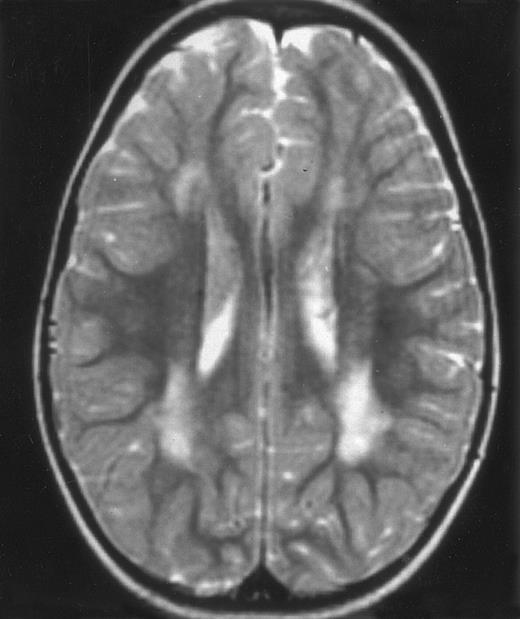

Three different aspects of brain imaging in HLH patients. (A) CT scan of a 3-month-old baby showing a large subdural effusion, several necrotic areas and hypodensities of the white matter. (B) Brain magnetic resonance of a 14-month-old boy showing large confluent areas of hypersignal in T2-weighted images. (C) Large symmetrical necrotic areas of cerebellar white matter in a 41/2-year-old girl (MRI).

Among the nine children with initial neurological symptoms, seizures were the most frequent initial symptom in the youngest patients, whereas ataxia was found in the two oldest patients (46 and 58 months old, respectively) (Table 1). All nine patients had the same CSF abnormalities as patients with meningitis only. Eight of these nine patients had a neuroradiological study performed at the time of their first neurological symptoms (Table 1). The two most frequent lesions were focal necrosis with parenchymal volume loss and atrophy (Fig 2A and C) and white matter abnormalities (Fig 2B). Several small focal lesions with hypersignal at MR imaging that enhanced after administration of gadopentate dimeglumine (or contrast on CT scan) were also observed in two cases.

Nine patients were transplanted soon after the remission of initial CNS and systemic manifestations. All of these patients had meningitis only as the CNS manifestation. The median delay between diagnosis and BMT was 4 months (range, 2 to 14 months). Two patients died of BMT-related toxicity (both recipients of an HLA-identical BMT). Seven patients are alive and well with normal neurological examination, normal CSF tap, and normal cognitive development after a follow-up of 18 to 132 months (median, 55 months) (four recipients of an identical BMT and three of a partially-identical BMT). After BMT, chimerism studies demonstrated full or partial engraftment in all of these seven patients. MRI was performed before and after the transplantation in three cases. Two patients had a normal MRI or an isolated subarachnoidal and subdural space dilatation before transplantation and a normal MRI, respectively 4 years and 18 months after transplantation. One patient had white matter abnormalities before transplantation, which remained identical 2 years after transplantation (Fig 4).

MRI of a symptom-free 31/2-year-old child who received BMT at 18 months showing the persistent white matter abnormalities.

Abnormalities on brain imaging appeared to roughly parallel the severity of clinical manifestations. All patients with neurological symptoms, but also half of the patients with initial meningitis, had abnormal brain imaging usually consisting of a combination of diffuse white matter abnormalities and necrotic areas with parenchymal volume loss, as previously described.8,23 In patients with isolated meningitis, however, only white matter abnormalities were detected, whereas necrotic lesions and cerebral atrophy were found in patients with neurological symptoms. These lesions progressed despite chemotherapy. Previous neuropathological studies have demonstrated infiltration by monocytes and activated lymphocytes of leptomeninges and brain parenchyma along penetrating vessels.24,25 Infiltration is associated with focal and confluent areas of myelin pallor, as well as neuronal loss, tissue necrosis, and cavitation,24,25 findings that were also demonstrated in the neuropathologic study of five patients in our series. Leukocytes infiltrating the CNS probably secrete cytokines and other neurotoxic factors, such as tumor necrosis factor-α (TNF-α), which may be responsible for the myelinic alteration observed in neurologically asymptomatic patients. Infiltrating leukocytes could also activate in parallel the numerous resident brain macrophages (the microglial cells) and astrocytes, which in turn, can secrete neurotoxic glutamate and free radicals.26